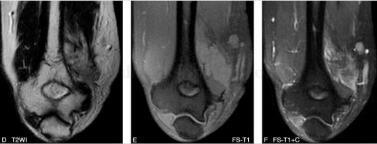

图3

(二)MRI

MRI能够直观地显示滑膜肉瘤的病灶形态、范围、与相邻关节、肌腱、滑膜及骨骼的关系。瘤体多表现为不规则,边缘呈分叶状,有时可见较清晰包膜。由于肿瘤常见囊变、出血、坏死以及钙化,因此MR信号不均。肿块内部的信号特点与其病理组织成分密切相关,T1WI上,肿块实体部分与周围肌肉信号相比表现为中等稍高信号,瘤体内的出血灶表现为点片状高信号,坏死或钙化区则表现为更低信号;

相应的T2WI上肿块实体部分表现为较高信号,坏死灶信号更高,钙化区表现为低信号,出血灶则信号不一,有时可见液-液平面;滑膜肉瘤较具特征性的MR表现是T2WI抑脂序列中,肿瘤表现为结节状稍高信号,结节呈大小近似的“卵石”状,其间有粗细不等的条状、网格状低信号间隔;增强扫描显示病灶不均一显著强化,病理证实系肿块内部含有丰富血窦。